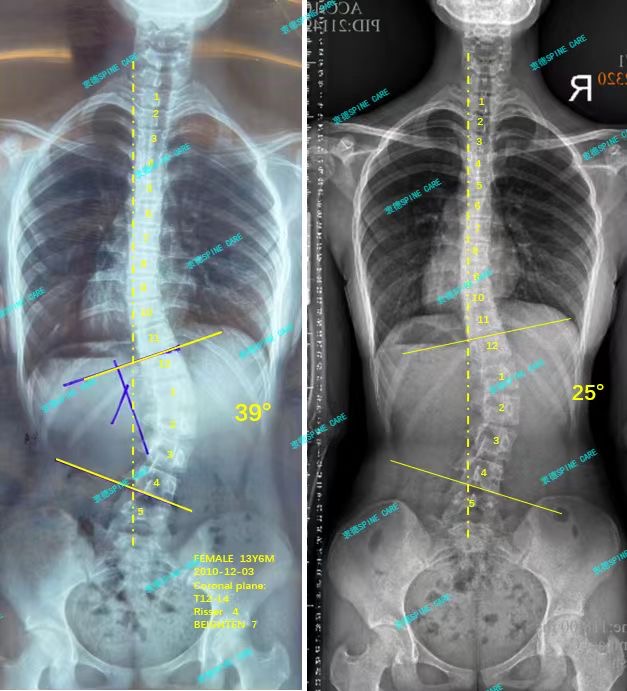

案例主人:萱萱 发现侧弯年龄:14岁 侧弯情况:Cobb角测39°

支具+ZDT训练1年后,我再次回到衷德复查,杨博士看了我的脱支x片并且评估了体态之后,告诉我我们我的39度侧弯降到了25度,旋转从14度降到6度,体态也明显改善了很多,我和妈妈都很满意这样的效果,我会坚持戴支具做训练,直到侧弯不再会加重。

One year after brace +ZDT training, I went back to Zhongde for a reexamination. After Dr. Yang saw my x-ray and evaluated my posture, he told me that my 39-degree lateral bending had dropped to 25 degrees, and the rotation had dropped from 14 degrees to 6 degrees, and my posture had also improved significantly. My mother and I are very satisfied with the effect. I will continue to wear braces for training until the lateral bending no longer gets worse.